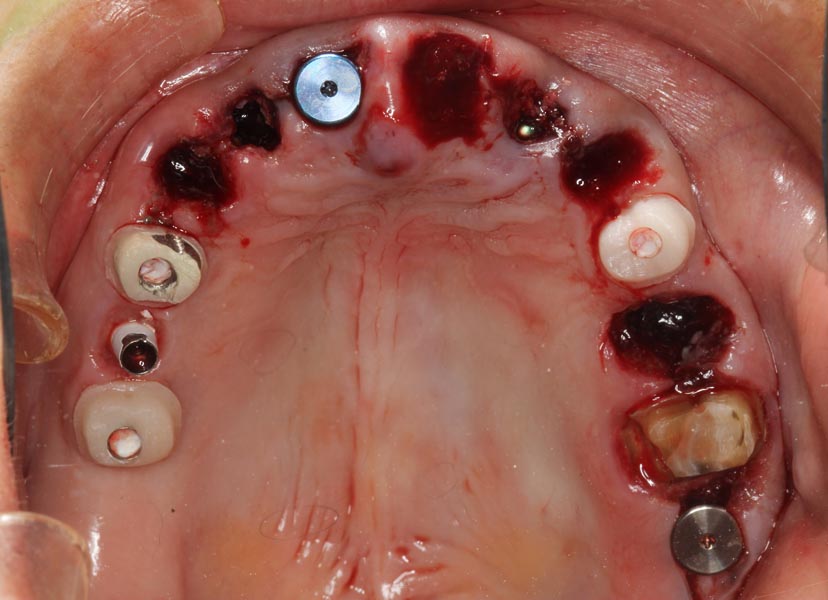

Smile GalleryImplant RestorationsFull Mouth Implant Restoration Full arch zirconia implant bridge (full smile) 1 of 37 Pre-op full smile Pre-op lips retracted Pre-op panoramic x-ray Extraction of strategic teeth Placement of implants Extraction of some remaining teeth after verification of adequate implant stability Occlusal view Post-op panoramic x-ray Immediately fabricated provisional restoration (tissue side view) Immediately fabricated provisional restoration (occlusal side view) Immediate provisional delivered on day of surgery Immediate provisional 2 weeks later Scalloped tissue developed from the provisional at 2 weeks Jig used for making a master impression Provisional in place (full smile) Provisional in place (lips retracted) Provisional in place (right side) Provisional in place (left side) Wax try-in (full smile) Wax try-in (right side full smile) Wax try-in (left side full smile) Wax try-in (full face, lips together) Wax try-in (full smile) Wax try-in (right side) Wax try-in (left side) Wax try-in (lips retracted) Full arch zirconia implant bridge on master cast (frontal view) Full arch zirconia implant bridge on master cast (occlusal view) Implant positions and soft tissue representation on master cast (occlusal view) Soft tissue representation on master cast (frontal view) Full arch zirconia implant bridge (tissue side view) Soft tissues on day of delivery (occlusal view) Soft tissues on day of delivery (frontal view) Full arch zirconia implant bridge delivered (lips retracted) Full arch zirconia implant bridge (lips retracted, close up) Post treatment panoramic x-ray Full arch zirconia implant bridge (full smile)